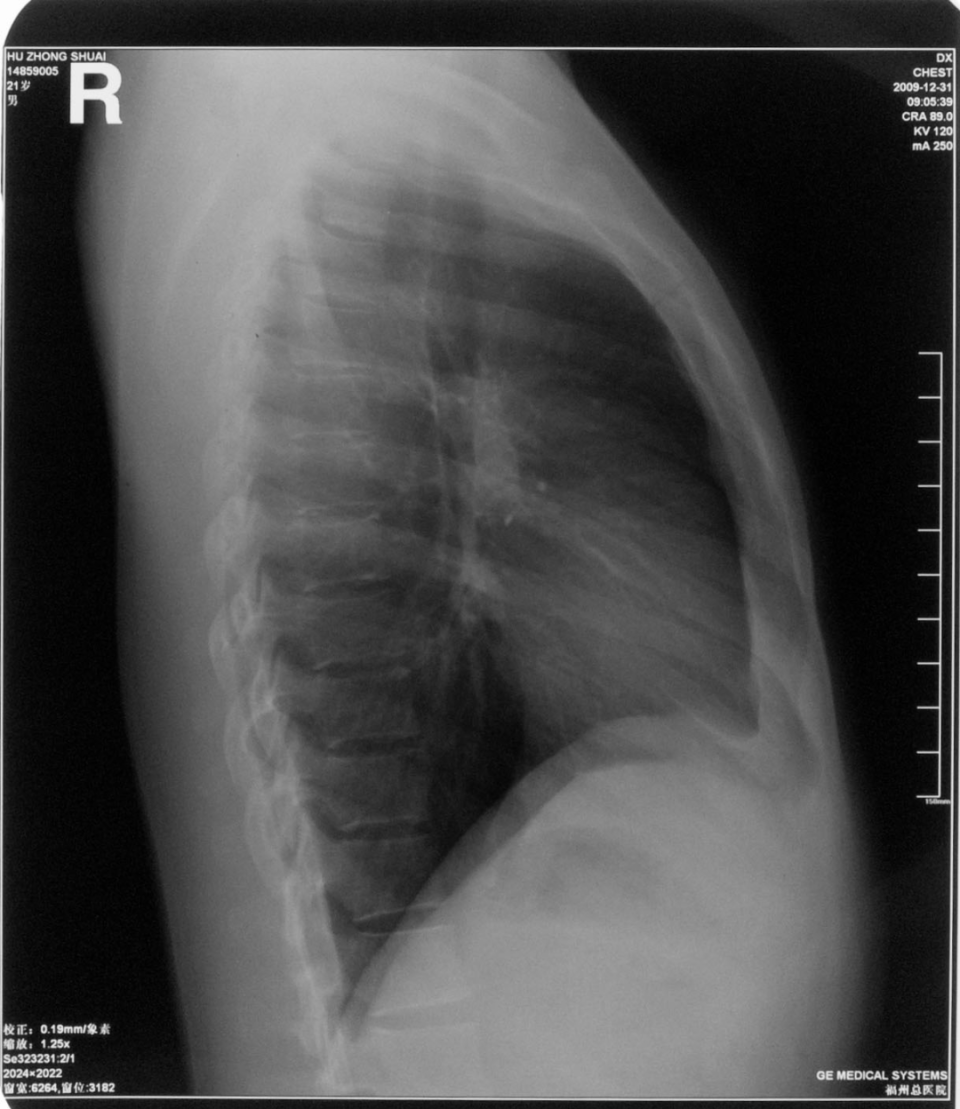

右肺下叶背段大叶性肺炎正侧位

图片

胸部正侧位片:右肺下叶背段见片状、三角形致密影,边缘模糊(箭头所指)